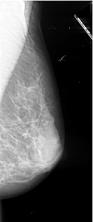

Mammografie

Hier wordt met behulp van een speciaal voor dit onderzoek ontworpen toestel foto's gemaakt van het borstweefsel. Hierbij wordt de borst samengedrukt om de weefsels beter in beeld te krijgen alsook om de stralingsbelasting zo laag mogelijk te houden.

Hier wordt met behulp van een speciaal voor dit onderzoek ontworpen toestel foto's gemaakt van het borstweefsel. Hierbij wordt de borst samengedrukt om de weefsels beter in beeld te krijgen alsook om de stralingsbelasting zo laag mogelijk te houden.